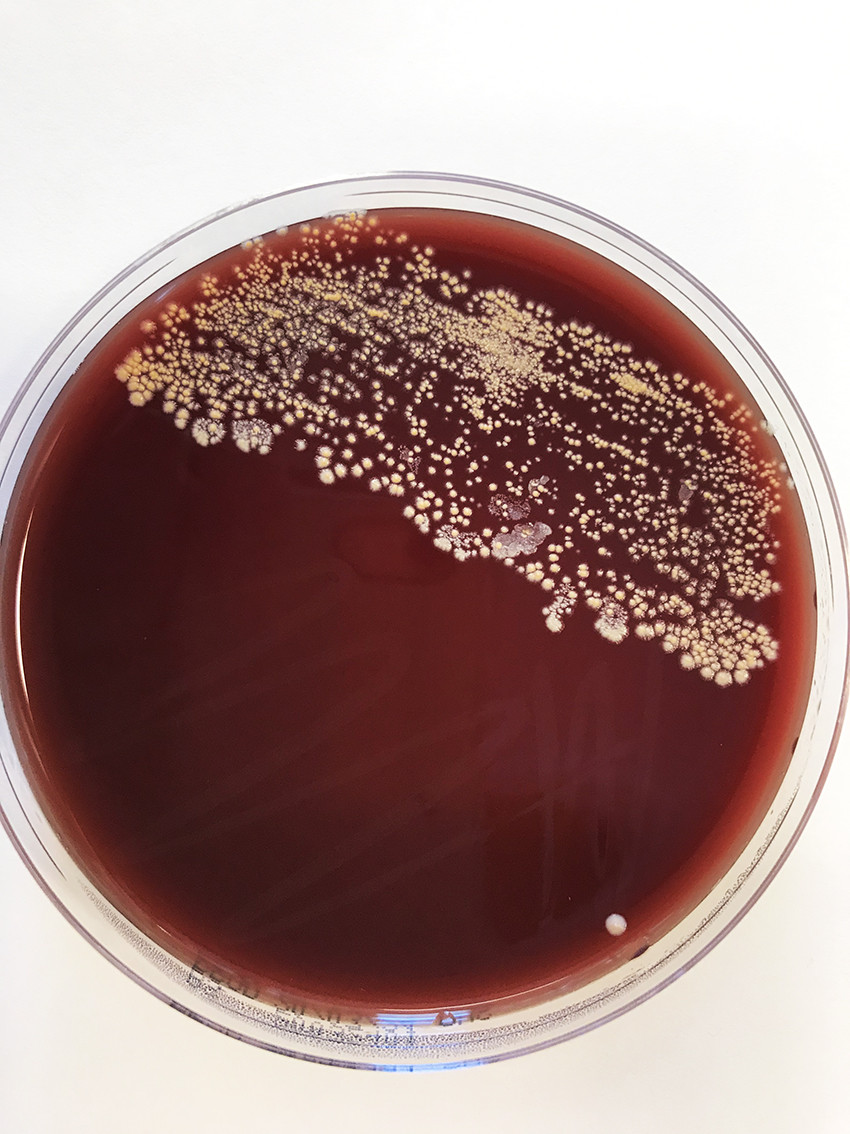

Two days after abscess drainage, there was abundant growth of Nocardia species pluralis (spp.) in a specimen from the abscess contents (Figure 3). In line with international recommendations, empiric combination treatment was initiated with high-dose intravenous trimethoprim/sulfamethoxazole, 15 mg/kg divided into 3–4 doses, and imipenem 500 mg four times daily (9, 10). The treatment with colchicine and methylprednisolone was discontinued due to the drugs' immunosuppressive effect.

Nocardia spp. are strictly aerobic, gram-positive, rod-shaped bacteria. Species in the genus are often slow-growing, and prolonged incubation times (7–10 days) may be required. The microbe grew on blood agar and was visible as dry chalky-white colonies after just 2 days (Figure 3). Microscopic examination of the colonies revealed gram-positive branching filamentous rods, which were partially acid-fast on Ziehl-Neelsen staining (Figure 4). Nocardia spp. are environmental bacteria found in soil and water worldwide. There are more than 80 different Nocardia species, of which at least 30 cause disease in humans, the most common being the N. asteroides complex, N. brasiliensis and N. farcinica (11).